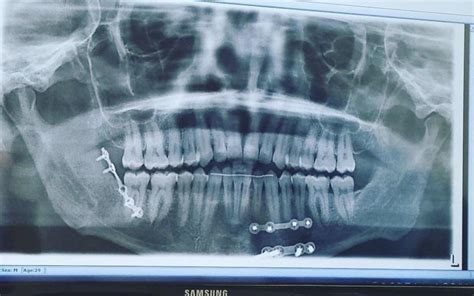

Disadvantages Of Jaw Wiring Maxillofacial Hardware Surgery T